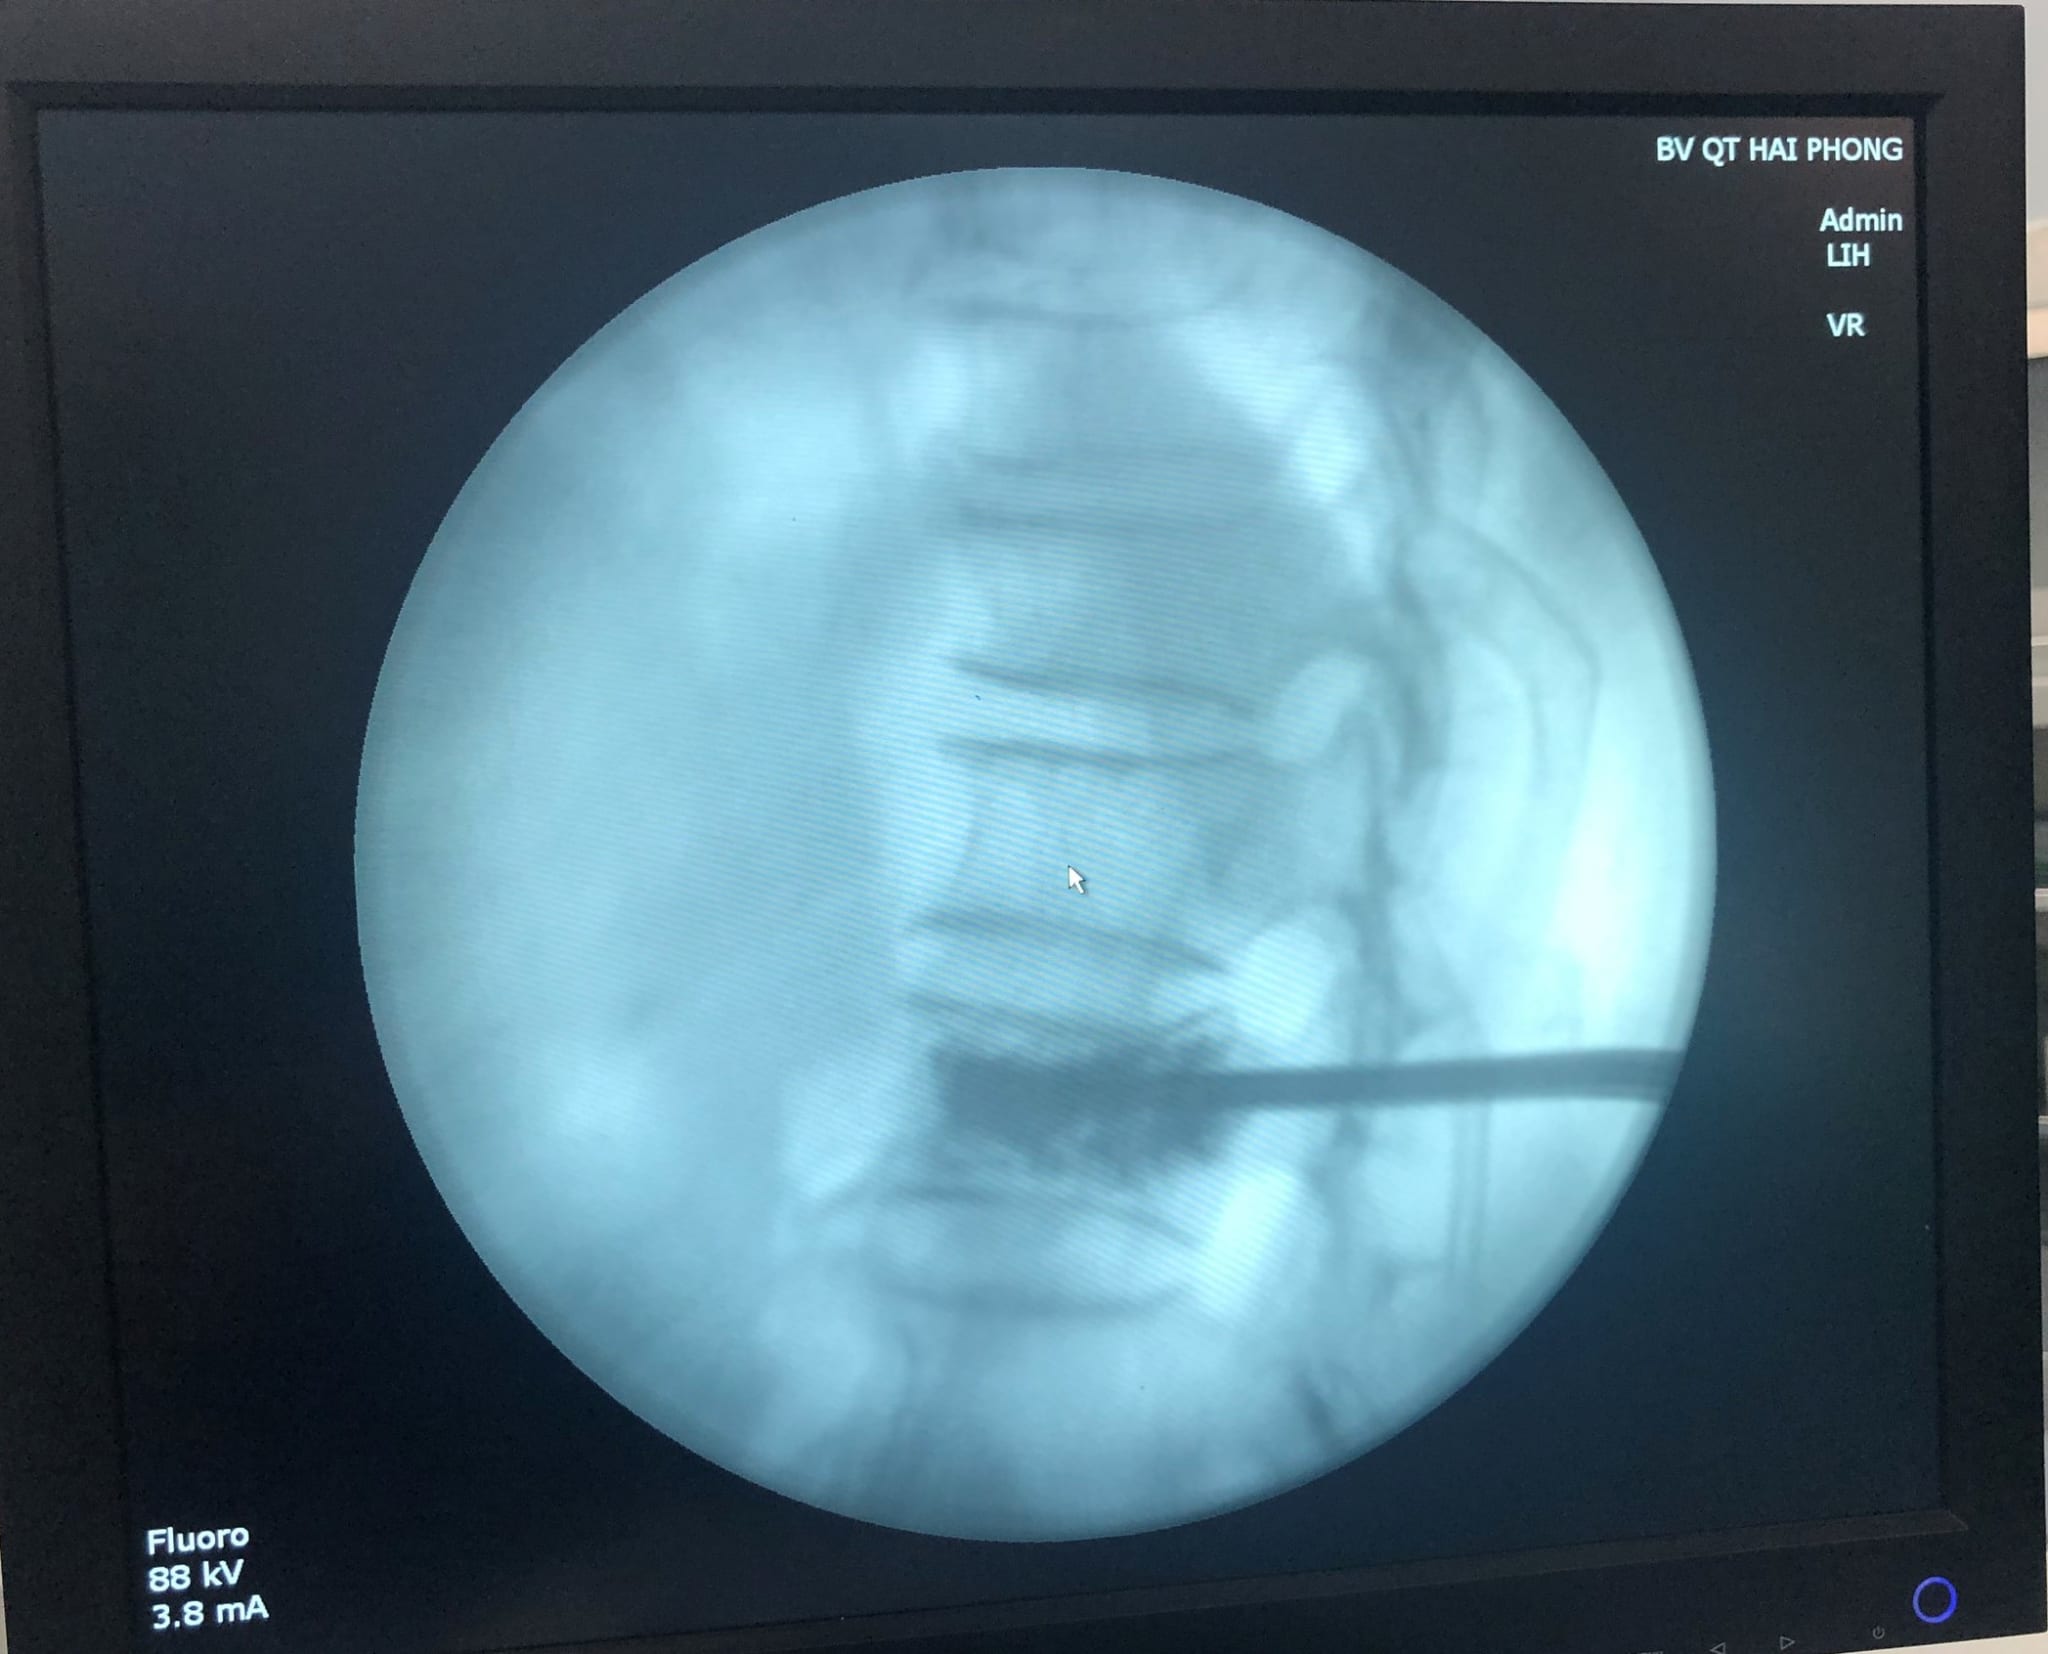

Không để người bệnh phải chịu cơn đau kéo dài thêm, các bác sĩ Khoa Ngoại đã nhanh chóng tiến hành hội chẩn và đưa ra phương pháp điều trị tốt nhất cho người bệnh đó là: Phẫu thuật tạo hình thân đốt sống bằng bơm cement sinh học không bóng. Ca phẫu thuật được thực hiện bởi BS. Nguyễn Mạnh Thuần; BS Vũ Đức Đạt – Khoa Ngoại Bệnh viện Đa khoa Quốc tế Hải Phòng. Dưới màn hình tăng sáng, bác sĩ đã dùng cement sinh học ở dạng lỏng bơm vào đốt sống gãy với mục đích hàn gắn, kết nối các mảnh gãy lại với nhau, từ đó không còn hiện tượng xô lệch các mảnh gãy gây đau đớn cho người bệnh.

BS. Nguyễn Mạnh Thuần; BS Vũ Đức Đạt – Khoa Ngoại Bệnh viện Đa khoa Quốc tế Hải Phòng thực hiện thành công phương pháp bằng bơm cement sinh học không bóng trong Phẫu thuật tạo hình thân đốt sống cho bệnh nhân